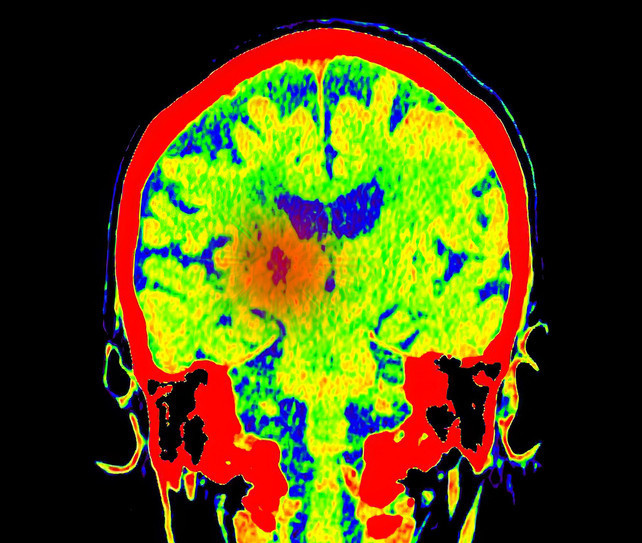

Hastanede triyaj odasına alınan ve kusmaya başlayan Moroney için dönüm noktası, annesinin tarama yapılması konusundaki sert ısrarı oldu. Yapılan BT taraması sonucunda beyninde bir tümör olduğu tespit edildi.

Daha sonra Cambridge’deki Addenbrooke’s Hastanesi’ne sevk edilen genç kıza burada acı haber verildi: Eğer tümör hemen alınmazsa bir ay içinde hayatını kaybedecekti. 17 Şubat’ta gerçekleşen başarılı bir operasyonla tümörün büyük bir kısmı temizlendi.

Ameliyat sonrası yapılan biyopsi, durumun tahmin edilenden daha karmaşık olduğunu ortaya koydu. Moroney’ye, genellikle 5 yaş altı çocuklarda görülen ve yetişkinlerde rastlanması son derece nadir olan 4. Evre Atipik Teratoid/Rhabdoid Tümör (AT/RT) teşhisi konuldu.